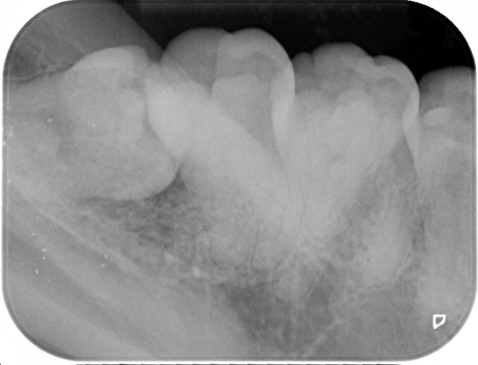

2.親知らずが虫歯になると、その手前の歯も虫歯になる可能性があります

一番右奥の親知らずは良く磨けず、虫歯になることが多いのです。早く抜いて、前の歯が虫歯にならないようにしなければなりません。

同じ症例をレントゲン写真で見たところです。親知らずが横倒しに生えていて、周りの骨を溶かしてしまっています。